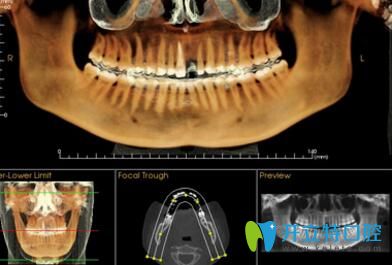

? 2、專業(yè)軟件分析:

? 一次3D掃描即可獲取全部原始記錄。在正畸治療計劃制定過程中為您創(chuàng)建全景片圖像、頭顱側(cè)位片圖像等所需影像。創(chuàng)建氣道分析所需的特定影像以及TMJ分析的校正圖像。利用可調(diào)節(jié)的失狀面視圖和立體透視功能,可以確定阻生和埋伏牙的位置。

長沙美萊口腔數(shù)字化矯正專業(yè)軟件分析